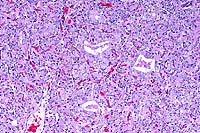

10x

obj

- Case14-3. Liver. There is diffuse dissociation of

hepatocytes, increased numbers of cells in the sinusioids, and

pale eosinophilic material (collagen) in centrilobular locations.

Central veins are inconspicuous. Kupffer cells contain abundant

pigment.

obj, Reticulin stain

- Case14-3. Liver. Reticulin stain demonstrates increased

sinusoidal reticulin extending from portal to centrilobular areas

of the liver.

40x

- Case14-3. Liver. This magnification shows abundant

reticulin and individualization of hepatocytes.

obj, Trichrome stain

- Case14-3. Liver. Blue staining areas localize collagen.